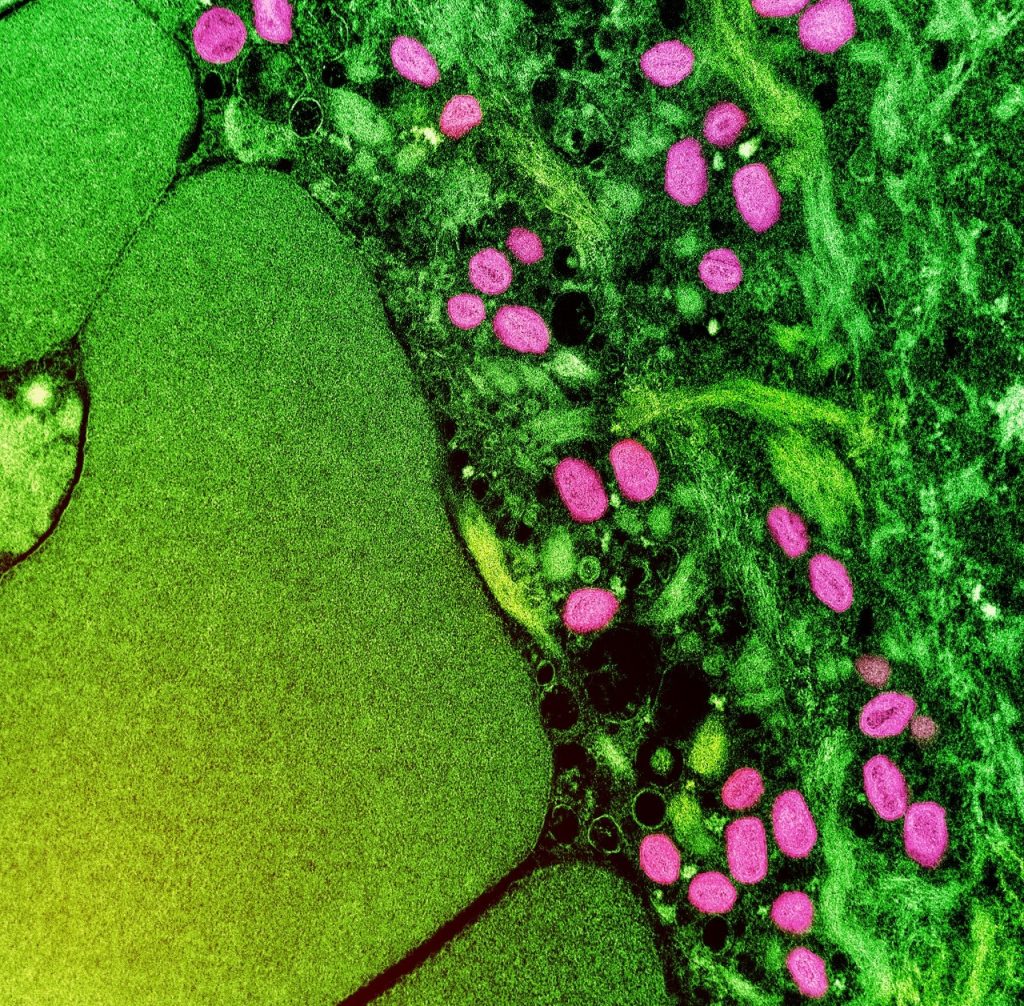

A Prefeitura de São Paulo confirmou o registro até o momento de três casos de varíola dos macacos (monkeypox) em crianças no município. São as primeiras notificações no público infantil. Conforme informou a Secretaria Municipal da Saúde, todas estão em monitoramento, sem sinais de agravamento.

Identificada pela primeira vez em macacos, a doença viral geralmente se espalha por contato próximo e ocorre principalmente na África Ocidental e Central. Raramente se espalhou para outros lugares, então essa nova onda de casos fora do continente causa preocupação. Existem duas cepas principais: a cepa do Congo, que é mais grave, com até 10% de mortalidade, e a cepa da África Ocidental, que tem uma taxa de mortalidade de cerca de 1%.